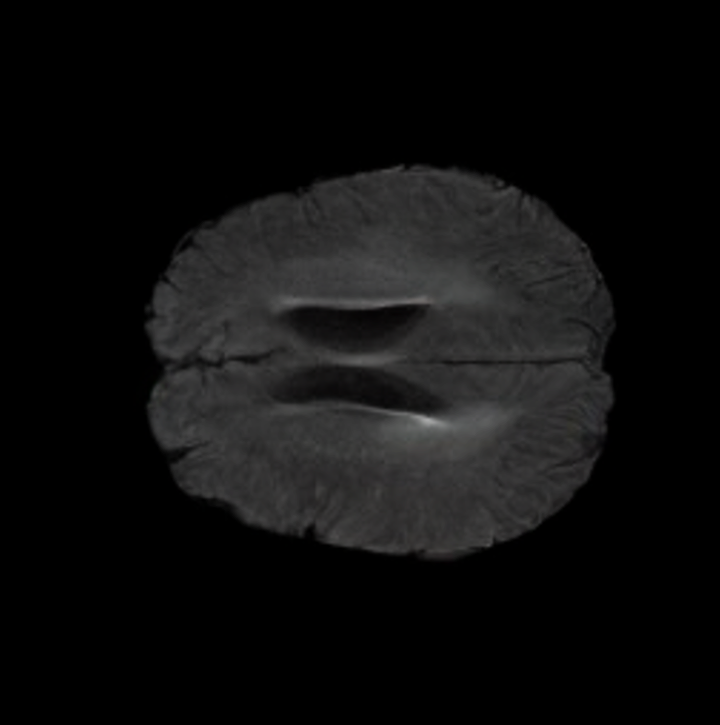

5.3 Out-of-Domain Generalisation

One way to test the generalization capability of the trained X-Diffusion is to test it on a completely different domain from an MRI dataset not seen during training. We report the single-slice results on NYU fastMRI [37, 82], a knee MRI dataset, using the X-Diffusion trained on the BRATS brain MRIs. The results are shown in Figure 9 and Table 2. It shows how successfully X-Diffusion is able to generate knee MRIs from a single image, despite not seeing knees at all in training. To qualitatively assess how realistic our generated 3D volumes were (produced from a single slice), we gave 20 generated examples alongside their real MRI counterparts to an expert orthopaedic surgeon. He was then asked to identify the real example from a given pair. The surgeon identified with certainty only 10 real knee MRIs out of 17, while could not decide on the remaining 3 of the 20 MRI pairs. This further validates the generated out-of-domain MRIs.